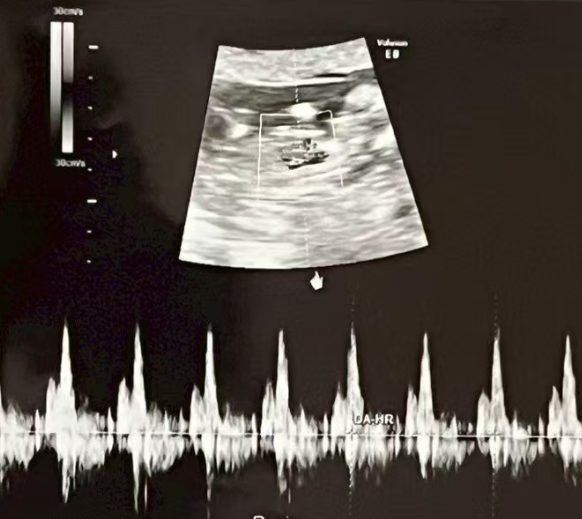

1月24日、妊娠7週。胎児の心拍を無事に確認できました。

小さな鼓動が確かに感じられ、

新しい命からの最初のメッセージを受け取ることができました。

今回の経過確認も順調で、母体の状態も良好です。